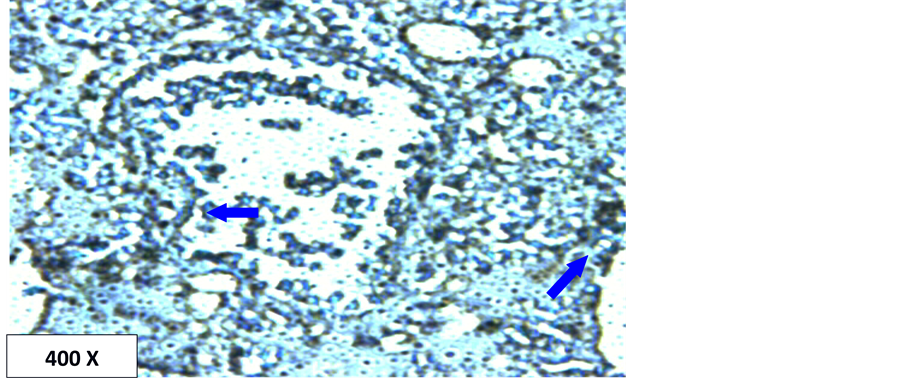

In the current study, the detection of p53 and Aspergillus antigen in lung tissues were investigated using immunohistochemistry technology. The results show that the Aspergillus is present in all used sample (100% of the infection) in the form of spores or hyphae (Table 1, Figures 1-3). It is also present within the blood vessels and within the interstitial spaces (Figure 2 and Figure 3). This high percent may be due to the highly specific and sensitive technique employed in this study (immunohistochemistry). Additionally, all cases in this study were from autopsy specimens, Autopsy specimens are more exposed to Aspergillus than other specimens. There may be relatively long time from death to obtain the specimens which may give a sufficient incubation time for the multiplication of Aspergillus.

When Mach-4 was used as a detection system which is a very highly sensitive detection system, the localization of Aspergillus is clearer even diffused within fluids (Figure 2 and Figure 3). The results show that all

Figure 2. Localization of Aspergillus spores in lung tissue using Mach-4 method. Brown color at the tip of the arrows indicates positive.